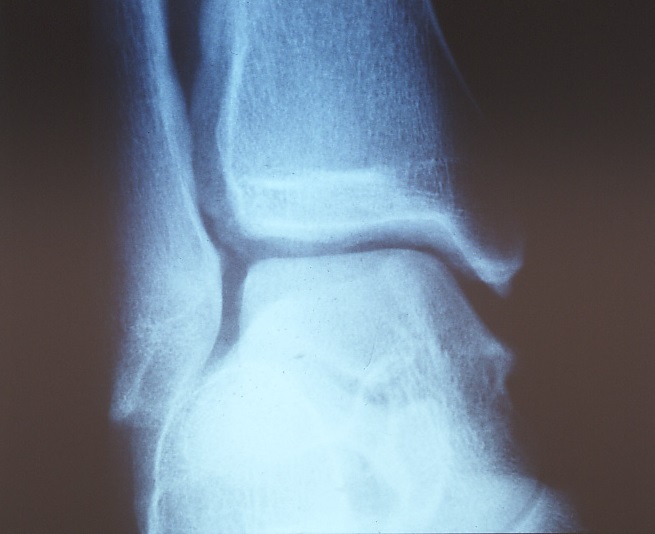

レントゲンチェックによる骨折の有無判定や、骨片の存在チェック、靱帯の緩みを調べるストレスレントゲン(写真3、4)、最近ではMRIや超音波検査で靭帯の有無、走行異常や肥厚像、出血などをチェックできます。

写真3 足関節は一見保たれている

写真4 同症例のストレスレントゲン写真は外側靱帯断裂のため足関節の傾きが明らかである。